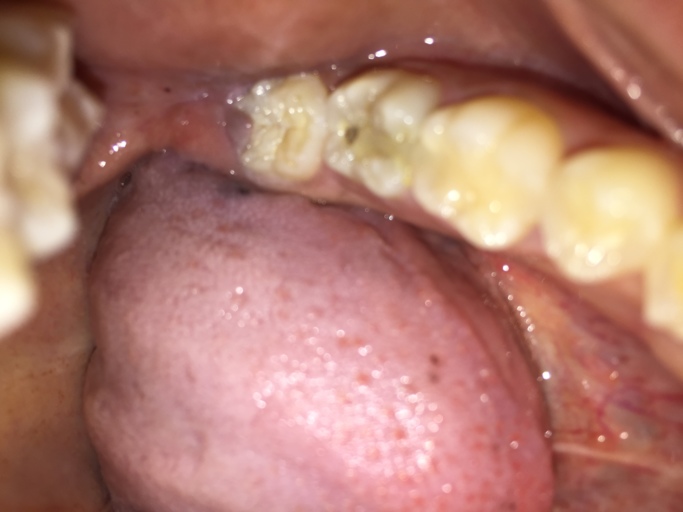

I had a composite filling on my molar tooth in the top row a couple weeks ago. But yesterday, I found my tongue lingering on that tooth, so I checked it out in the mirror, and it appears that a hole has appeared in my filling! It wasn't on the natural part of the tooth, but the filling. It was on the front, and it's quite a big hole, if I'm going to be honest with you, and I'm not very sure, but it seems to have appeared overnight or something. I flick my tongue in my mouth a lot, and I didn't feel anything 'unusual' in my teeth before. It might be that it already existed before, but I didn't notice, though. It doesn't hurt either, but I am still quite concerned. Did the filling break down or do I have a cavity again? I brush very carefully 2 times a day, for more than two minutes. I use mouthwash two hours after brushing at night and floss once a day. I use an electrical toothbrush. If it is a cavity, am I doing anything wrong with my oral hygiene routine? I'm very sorry about the blurry picture! It's not clear, but I hope you can see that there's a hole in the right molar tooth when it's compared to the one at the left side. There should be something covering the front up in the right molar tooth, but the whole chunk of that is gone. I'm also very sorry for the long text, but thank you to the people who read this to the end and to the answers in advance, too.(And if you are wondering why I have such little teeth in the picture, I have a genetic condition where my teeth doesn't grow back after it's baby version fell.)